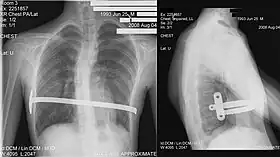

X-Ray of a 15-year-old male after undergoing the procedure